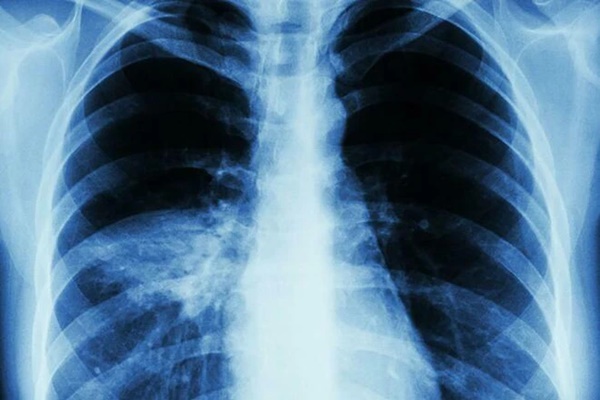

Sắc da chuyển sang màu ngăm đen cảnh báo bệnh phổi tấn công

Sắc da chuyển sang màu ngăm đen cảnh báo bệnh phổi tấn công.